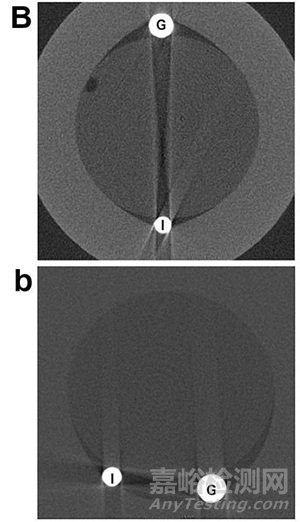

圖6[12].B:固有導(dǎo)絲球囊,I為固有導(dǎo)絲,G為導(dǎo)引導(dǎo)絲;b:導(dǎo)絲移位靠近另一導(dǎo)絲。

刻痕球囊(scoring balloon,SB)的設(shè)計(jì)理念源于雙導(dǎo)絲技術(shù),即在球囊外再置入一條額外的伴行導(dǎo)絲,當(dāng)球囊擴(kuò)張時(shí),外部伴行導(dǎo)絲應(yīng)力集中,從而有效地壓碎硬的斑塊。但固有導(dǎo)絲球囊在擴(kuò)張時(shí)導(dǎo)絲易發(fā)生移位[12](如圖6所示)。研究者[12]在兩種硬度的硅膠管中擴(kuò)張三種球囊,通過計(jì)算附加元件進(jìn)入硅膠管的深度與元件高度的比例分析球囊對(duì)血管的切割程度,CB比NSE和固有導(dǎo)絲球囊切割得更深(結(jié)果如表1所示),且刀片元件無明顯變形,而棘突元件、固有導(dǎo)絲均有不同程度的變形。